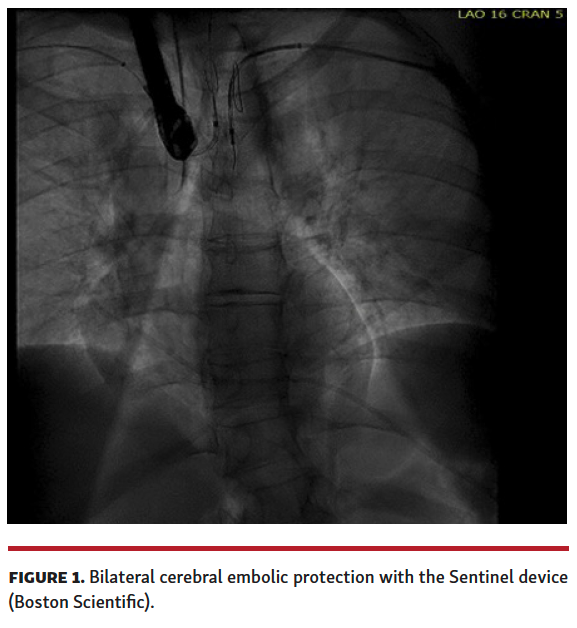

The patient’s iliofemoral and subclavian vessel size precluded percutaneous cannulation. We decided to perform transcaval aortic access to facilitate passage of a 26 Fr DrySeal cannula (Gore Medical).

Given the proximity of the thrombus to the left subclavian, bilateral cerebral embolic protection was performed with 2 Sentinel cerebral embolic protection devices (Boston Scientific) (Figure 1). We then obtained transcaval access using standard technique (Figure 2) and a 26 Fr DrySeal sheath was placed across the retroperitoneum into the abdominal aorta. A 17 Fr cannula (Edwards Lifesciences) was placed into the contralateral vein to serve as the AngioVac return cannula. A 180° Gen 3 AngioVac catheter was then prepped in standard fashion and advanced through the 26 Fr DrySeal sheath; it was then engaged with transesophageal echocardiography guidance in the aortic thrombus, and the mobile part was successfully aspirated (Figure 3 and Video 2) with small residual clot that was adherent to the aortic wall (Video 3). The patient was discharged on therapeutic warfarin.